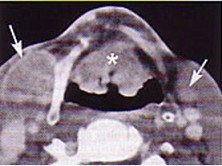

4.下面是一頸部CT圖,其中結構標志不正確的是  (    )

正確答案:D

6.CT檢查見下圖,進一步的檢查是  (    )